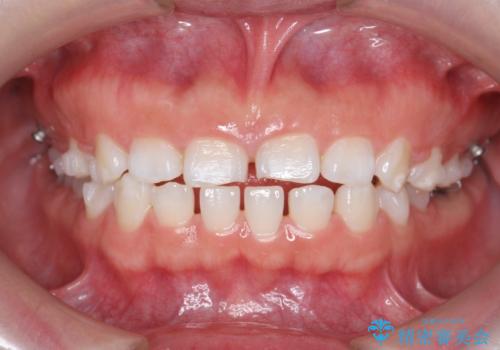

インビザライン 気になるすきっ歯の改善

- 上下顎前歯部の空隙が気になるので治したいと当院にいらっしゃった方の症例です。

非抜歯、インビザラインによる矯正治療により歯と歯の隙間および前歯の上下の隙間を閉じ切りました。